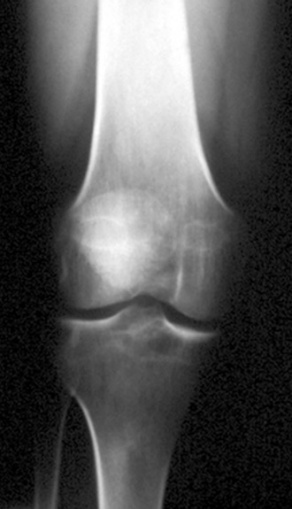

PVNS